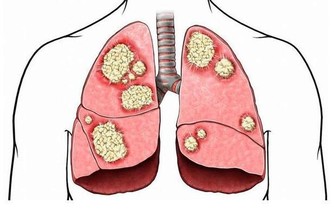

秋天容易感冒。如果肺部虛弱,就不足以抵禦外界的空氣,肌肉表面不結實,容易出汗,易受外界有害氣體的侵襲而常感冒,而外界有害氣體侵入肌肉表面,並常引起肺部疾病。皮膚由肺部支配。

4、聲音嘶啞肺氣豐富的人的聲音是響亮的,肺氣弱的人的聲音是低的。當風寒襲肺時,肺氣被堵塞,有可能出現嘶啞的現象。